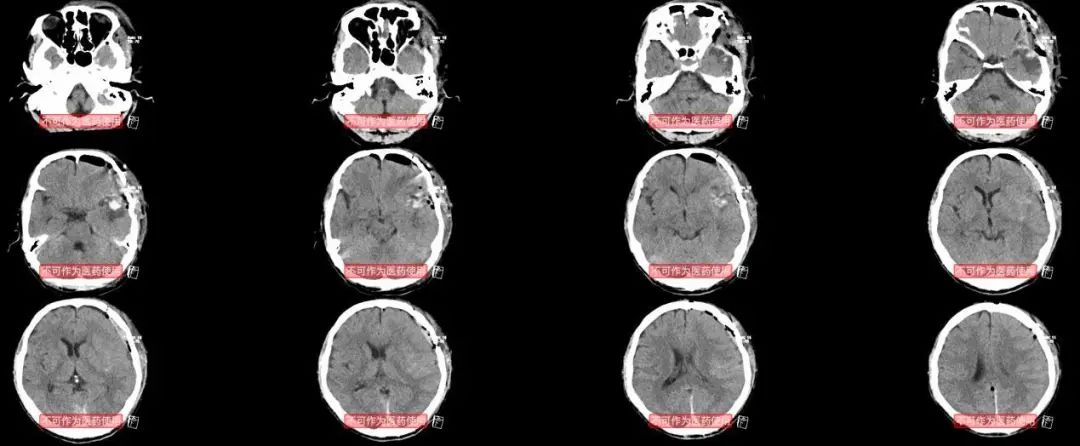

9月9日的头颅CT,病人基本清醒了,就是感觉呼吸困难,呼吸快,血氧饱和度90%左右。追问病史病人答:术前每天吸烟3包(虽然住院后没有抽烟)。次日呼吸更困难了,血氧饱和度有时可以60%,立即复查胸部CT。

胸部CT显示极其严重的肺部感染,记得1年前一个病人因为这样严重的肺部感染(当然那例病人是后颅窝肿瘤,术后可能后组颅神经损伤,可能存在误吸),后来严重ARDS,气管切开,转入MICU治疗了很长时间,费用超过30万。

9月14号的CT,肺部就有好转,病人的病情也明显好转。

9月26号胸部CT明显好转后出院。